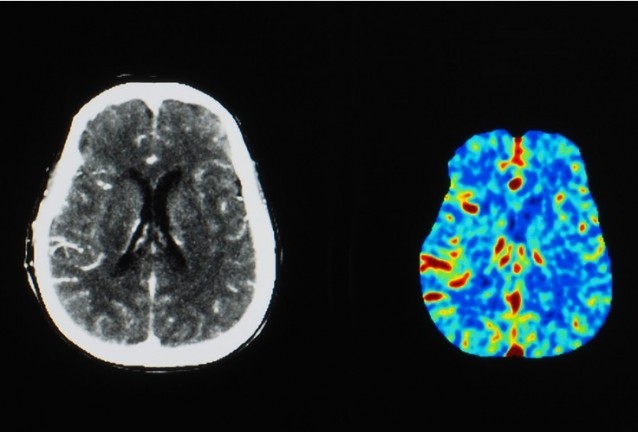

Ядрено-магнитният резонанс (ЯМР) с повишен контраст е често срещан вид диагностика; повече от 30 милиона процедури се извършват годишно в целия свят. Безопасността на контрастните вещества на базата на гадолиний (GBCA), които в момента се използват за такива ЯМР, наскоро беше поставена под въпрос.

Що се отнася до способността да се контрастира, учените я тестваха в проучване върху мишки. Експертите сравниха ефективността на новия контрастен агент Mn-PyC3A с два съвременни GBCA (Gd-DOTA и Gd-EOB-DTPA) при откриването на тумори при миши модел на рак на гърдата и метастатичен рак на черния дроб.

Състезанието за точност на диагностиката с Gd-DOTA завършва почти наравно, като Mn-PyC3A се елиминира от тялото много по-бързо. На фона на Gd-EOB-DTPA обаче новият контраст търпи загуба. Учените обясняват това с факта, че в този случай диагнозата се отнася до рак на черния дроб, докато черният дроб е основният орган, който допринася за изхвърлянето на манган от тялото. И това е, което затруднява диагностиката.